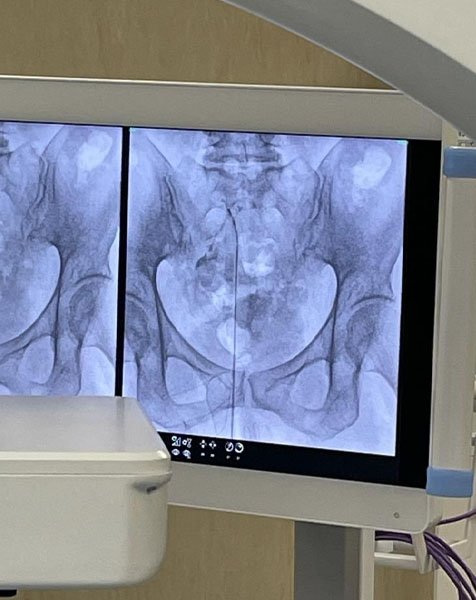

L’epidurolisi è una tecnica mininvasiva che prevede, sotto guida fluoroscopica ed in anestesia locale o blanda sedazione, l’introduzione di un catetere/elettrodo che attraverso una lisi meccanica e farmacologica, permette lo sbrigliamento delle radici nervose riducendo così la sintomatologia dolorosa. È possibile, inoltre, attraverso la punta di questo particolare elettrodo, eseguire la radiofrequenza pulsata gangliare a più livelli.

CASE STUDY EPIDUROLISI